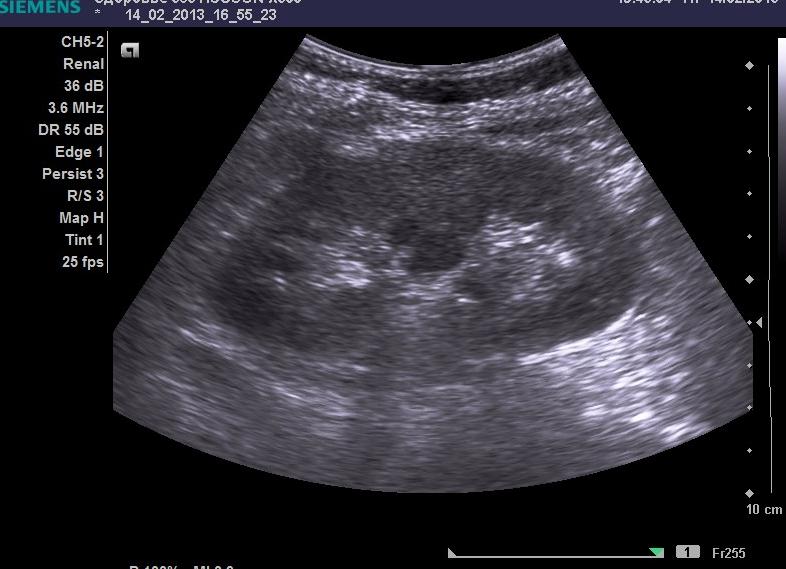

Как проводят УЗИ в урологии?

Методика исследования предполагает прохождение ультразвукового луча, испускаемого датчиком аппарата, сквозь ткани и органы человека. Часть эхосигналов отражается, приобретая на экране вид полосок различного цвета: чем плотнее структура, тем светлее изображение. Так, камни будут выделяться белым цветом, а жидкость – черным.

УЗИ проводится на кушетке. Для визуализации органа необходимо, чтобы пациент повернулся набок. Часто параллельно врач осматривает мочевой пузырь (пациент лежит на спине), брюшную полость и смежное пространство. Все необходимые данные доктор получает за 15-20 минут.

Показатели нормы

Осматривая почку, врач оценивает ее расположение, размеры паренхимы органа и лоханок, наличие аномалий строения, наличия кист, конкрементов, онкологических образований.

В норме органы расположены на уровне 1 или 2 поясничного позвонка, левая на 1-2 см ниже. Для взрослого человека, в том числе и для беременной женщины, толщина паренхимы не должна превышать 20-22 мм. Показатели, длины, ширины, толщины равны 10-12 мм, 5-6 мм, 4-5 мм, соответственно. Паренхима — однородная, без включений. В лоханке не должны наличествовать конкременты.

Результаты проведенного исследования выглядят в виде черно-белой фотографии и письменного заключения специалиста. В случае обнаружения патологических изменений – конкременты, кистозные образования, опухоли, они обязательно будут отображены на фотоснимке.

В нормальных показаниях, почечные структуры взрослого человека, могут иметь следующие характеристики – длина почки в пределах 11-13 см, ширина органа 6-7 см, толщина не более 5-6 см, толщина почечной ткани составляет 1.5 – 2.5 см.

Стоит отметить, что левая и правая почки у человека могут быть разными по размеру, но не больше чем на 2-3 см по каждому из показателей. Форма органа должна представлять боб. Расположение почки – за брюшинной, по равные степени с боков позвоночного столба, на уровне 12 грудного позвонка и 2 поясничного.

Замечено, что физиологически – правая почка несколько ниже левой. Почки должны быть в нормальной степени окутаны жировой клетчаткой.